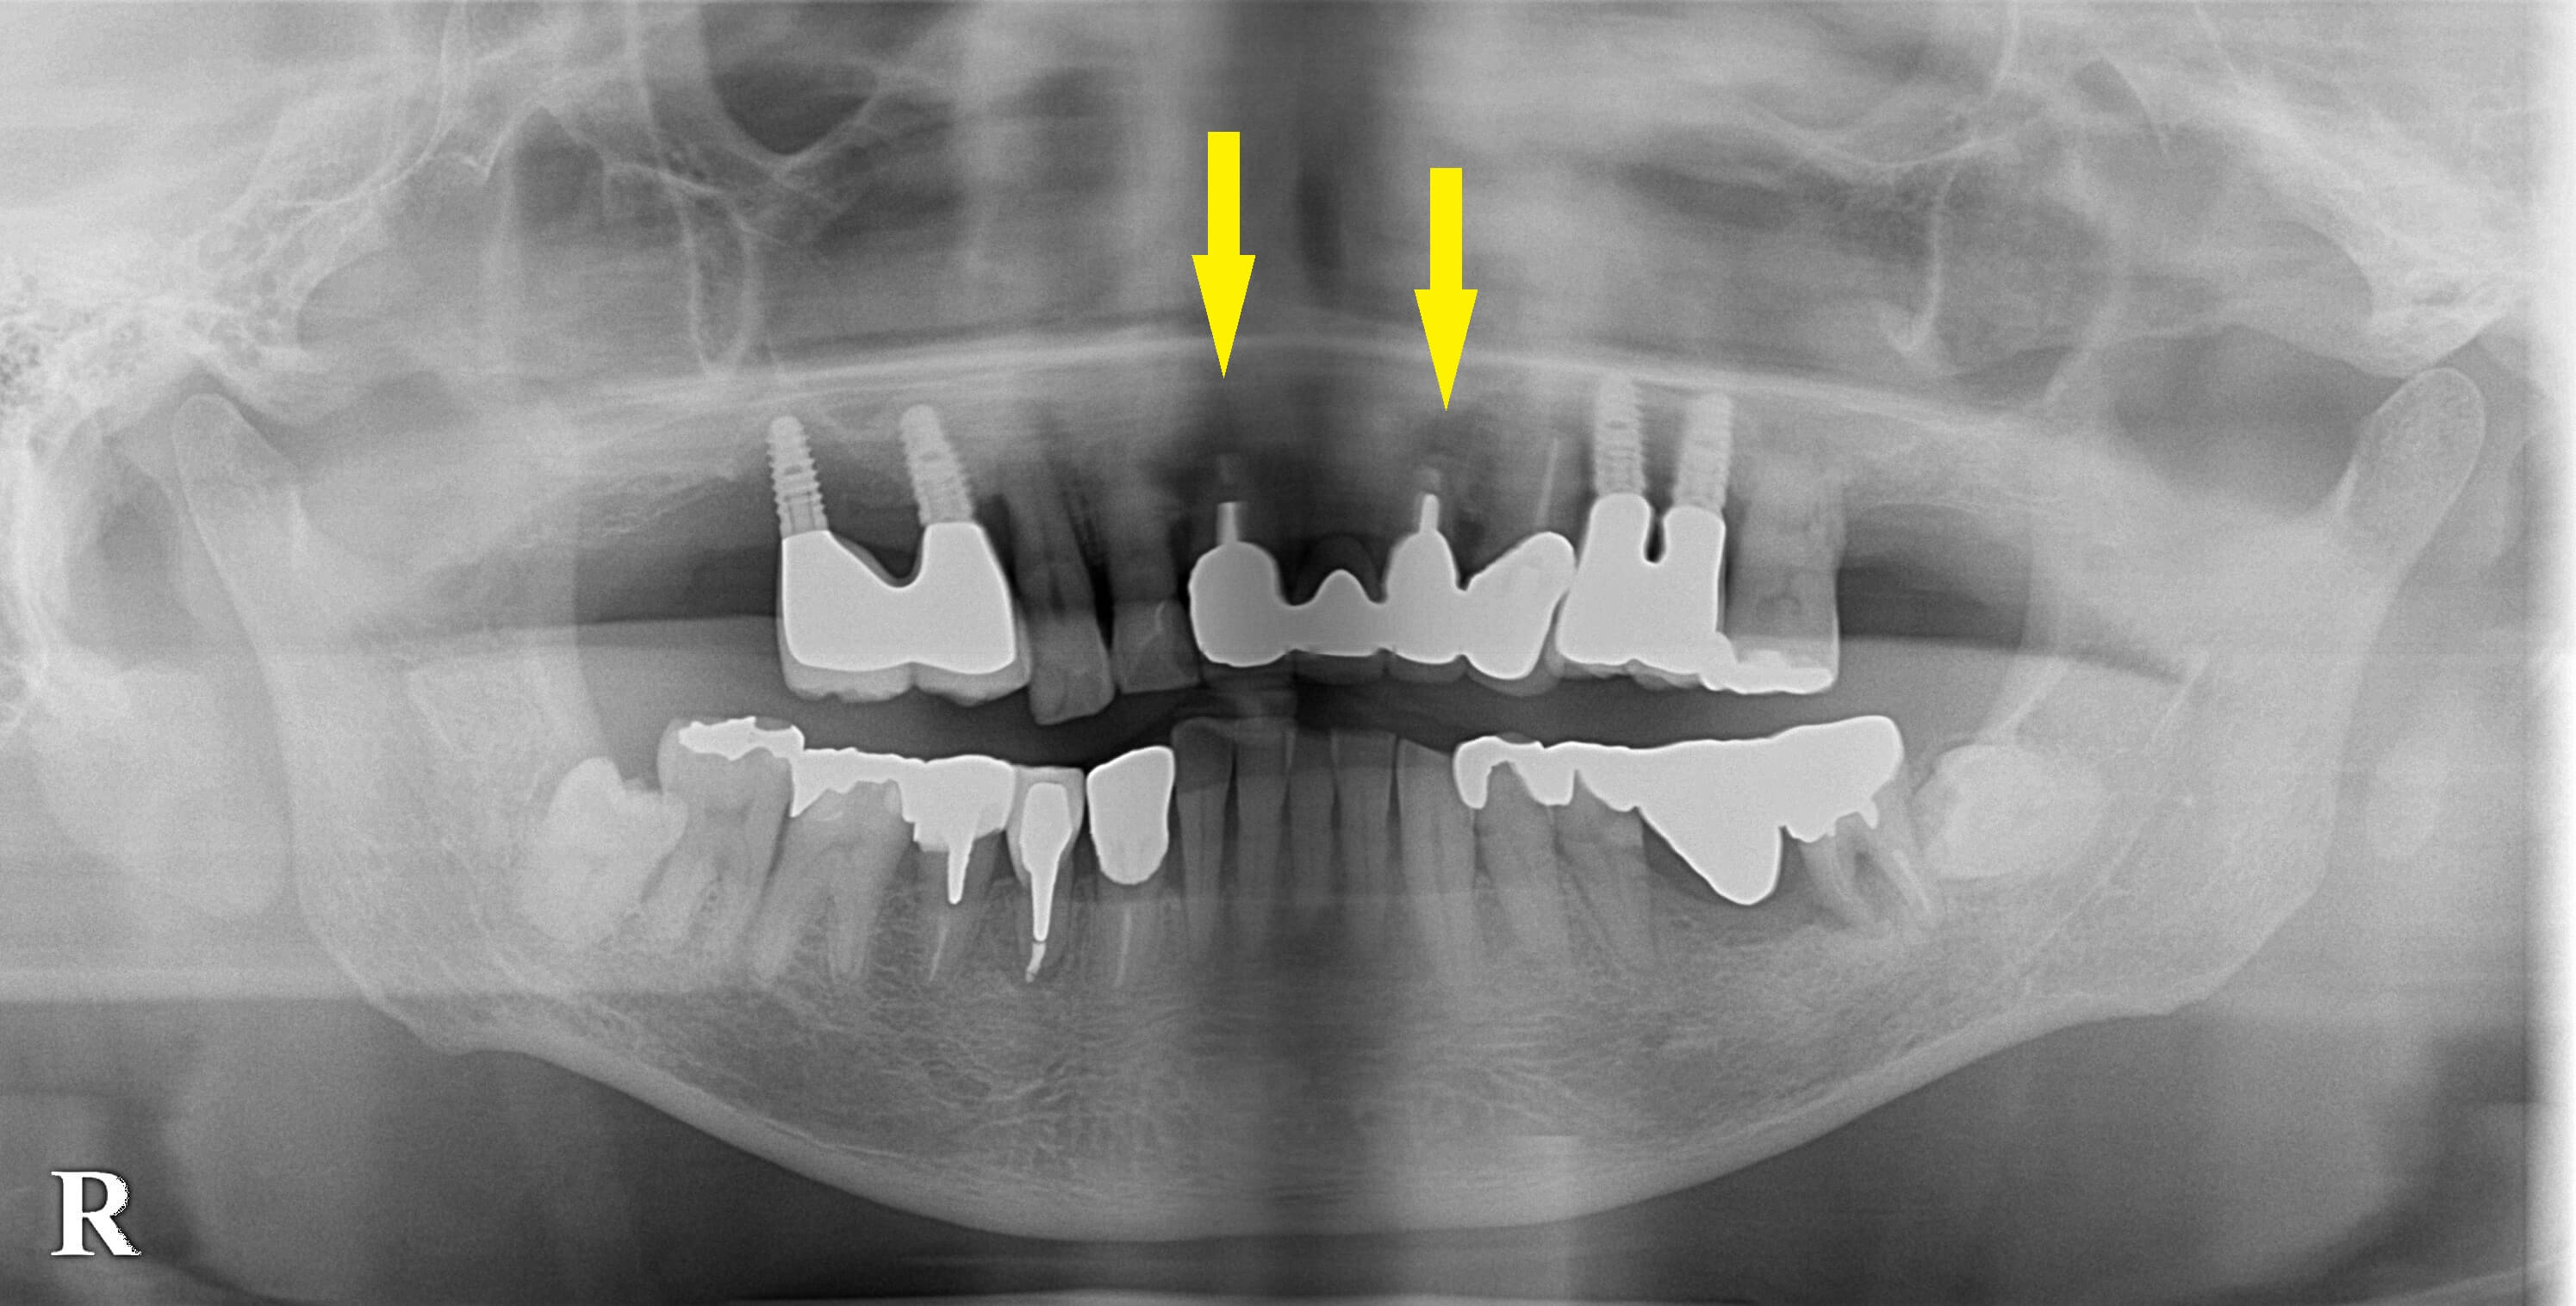

患者様は名古屋在住の60代男性。

以前に左右の上顎臼歯部にインプラント治療を行った患者様です。

今回、上顎の前歯のブリッジにしていた歯が破折し、抜歯を余儀なくされました。

この部位もインプラント治療を希望されましたので、2本のインプラント埋入を行い、インプラントでブリッジを計画しました。

しかし、2本とも骨の幅が薄く(2段目の左右の写真)、通常埋入が困難であったので、インプラントの外側に骨補填材を充填して、骨幅を増やす手術を行いました。